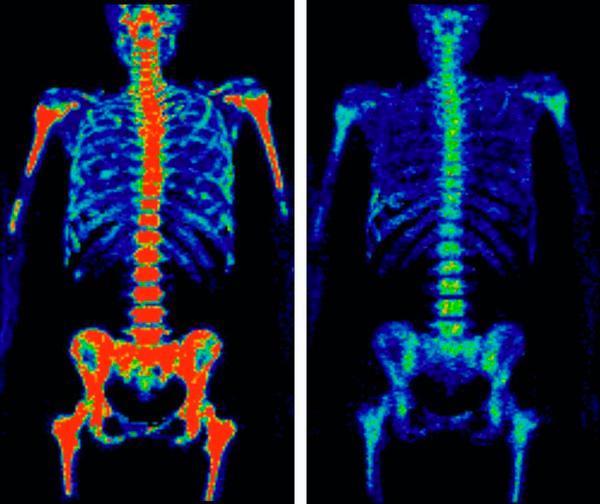

The organ where the cancer first spread matters a lot. Liver metastases often signal a tougher battlehence the phrase stage4 cancer survival rate liver appears in many searches. Bone or brain lesions can cause specific symptoms but dont always cut survival as sharply as liver involvement.